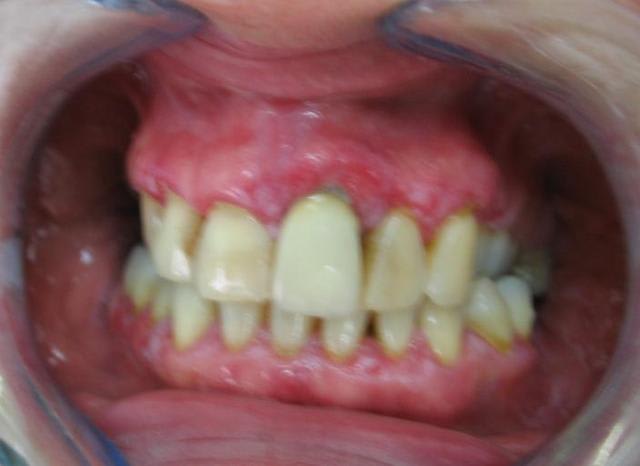

patiente de 50ans, consulte pour douleur et saignement gingival.

problème hépatique sous traitement( diagnostic précis non obtenu),pas d'autre medicament pris.

premier traitment il y a un mois : 10j jour de metronidazole à 1.5g/j puis traitement eau oxygéné+ bicarbonate + prexidine 1mois.

moins de douleur mais toujours les ulcérations.

la muqueuse est souple au touché ,inflammée, des poches sont presentes mais modérées 3-5mm.

les photos sont moyennes mais à mon avis il y a un lichen plan generalisé arrete l'eau oxygénée ( aggrave le lichen plan) et prend contact avec le gastro entero car il y a un rapport entre ses pbs hepatiques et le lichen plan peut être

fais une biopsie qui te permettra très vite de poser le diag

photo d'un lichen plan erosif pour comparer avec ce que tu as en bouche et la discussion eugenolienne